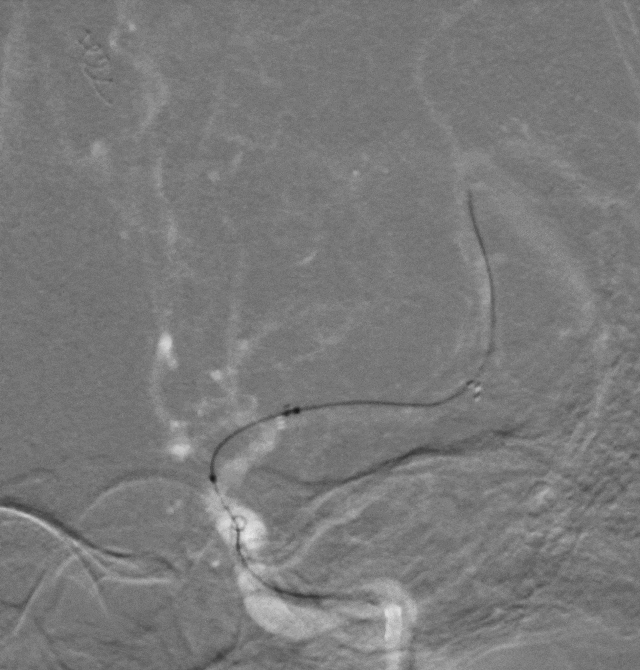

拟行球囊扩张术治疗支架内狭窄。

术中器械

6F 088in内径 通桥玄武™长鞘

2.0mm*15mm 通桥白驹®颅内球囊扩张导管

通桥银蛇®颅内支持导管

2.0*15mm 紫杉醇球囊

手术过程:

治疗术后效果: